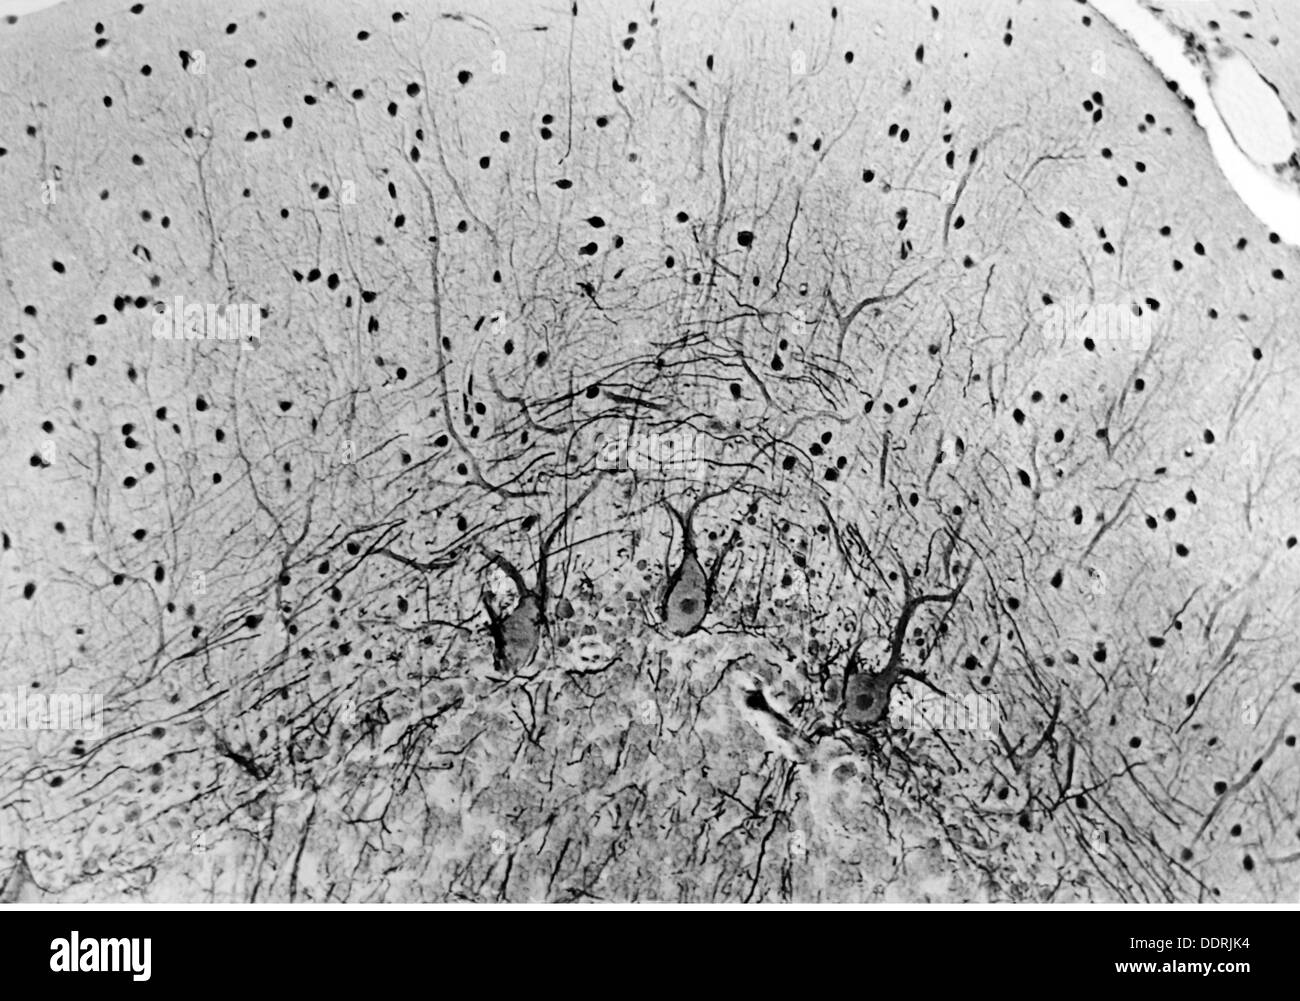

medicine, anatomy, cerebric / cranium, nerve cell of the human cerebellum, 20th century, 20th century, microscopy, nerve cell, nerve cells, neural, neuritic, nerve pathway, nerve tract, nerve pathways, nerve tracts, cerebellum, medicine, medicines, historic, historical, Additional-Rights-Clearences-Not Available Stock Photohttps://www.alamy.com/image-license-details/?v=1https://www.alamy.com/medicine-anatomy-cerebric-cranium-nerve-cell-of-the-human-cerebellum-image60141160.html

medicine, anatomy, cerebric / cranium, nerve cell of the human cerebellum, 20th century, 20th century, microscopy, nerve cell, nerve cells, neural, neuritic, nerve pathway, nerve tract, nerve pathways, nerve tracts, cerebellum, medicine, medicines, historic, historical, Additional-Rights-Clearences-Not Available Stock Photohttps://www.alamy.com/image-license-details/?v=1https://www.alamy.com/medicine-anatomy-cerebric-cranium-nerve-cell-of-the-human-cerebellum-image60141160.htmlRMDDRJJG–medicine, anatomy, cerebric / cranium, nerve cell of the human cerebellum, 20th century, 20th century, microscopy, nerve cell, nerve cells, neural, neuritic, nerve pathway, nerve tract, nerve pathways, nerve tracts, cerebellum, medicine, medicines, historic, historical, Additional-Rights-Clearences-Not Available

medicine, anatomy, cerebric / cranium, cortices of the human cerebellum, photo by Dr. Adelheid Winkelmann, 20th century, 20th century, microscopy, nerve cell, nerve cells, neural, neuritic, nerve pathway, nerve tract, nerve pathways, nerve tracts, cerebral cortex, cerebellum, medicine, medicines, historic, historical, Additional-Rights-Clearences-Not Available Stock Photohttps://www.alamy.com/image-license-details/?v=1https://www.alamy.com/medicine-anatomy-cerebric-cranium-cortices-of-the-human-cerebellum-image60141176.html

medicine, anatomy, cerebric / cranium, cortices of the human cerebellum, photo by Dr. Adelheid Winkelmann, 20th century, 20th century, microscopy, nerve cell, nerve cells, neural, neuritic, nerve pathway, nerve tract, nerve pathways, nerve tracts, cerebral cortex, cerebellum, medicine, medicines, historic, historical, Additional-Rights-Clearences-Not Available Stock Photohttps://www.alamy.com/image-license-details/?v=1https://www.alamy.com/medicine-anatomy-cerebric-cranium-cortices-of-the-human-cerebellum-image60141176.htmlRMDDRJK4–medicine, anatomy, cerebric / cranium, cortices of the human cerebellum, photo by Dr. Adelheid Winkelmann, 20th century, 20th century, microscopy, nerve cell, nerve cells, neural, neuritic, nerve pathway, nerve tract, nerve pathways, nerve tracts, cerebral cortex, cerebellum, medicine, medicines, historic, historical, Additional-Rights-Clearences-Not Available